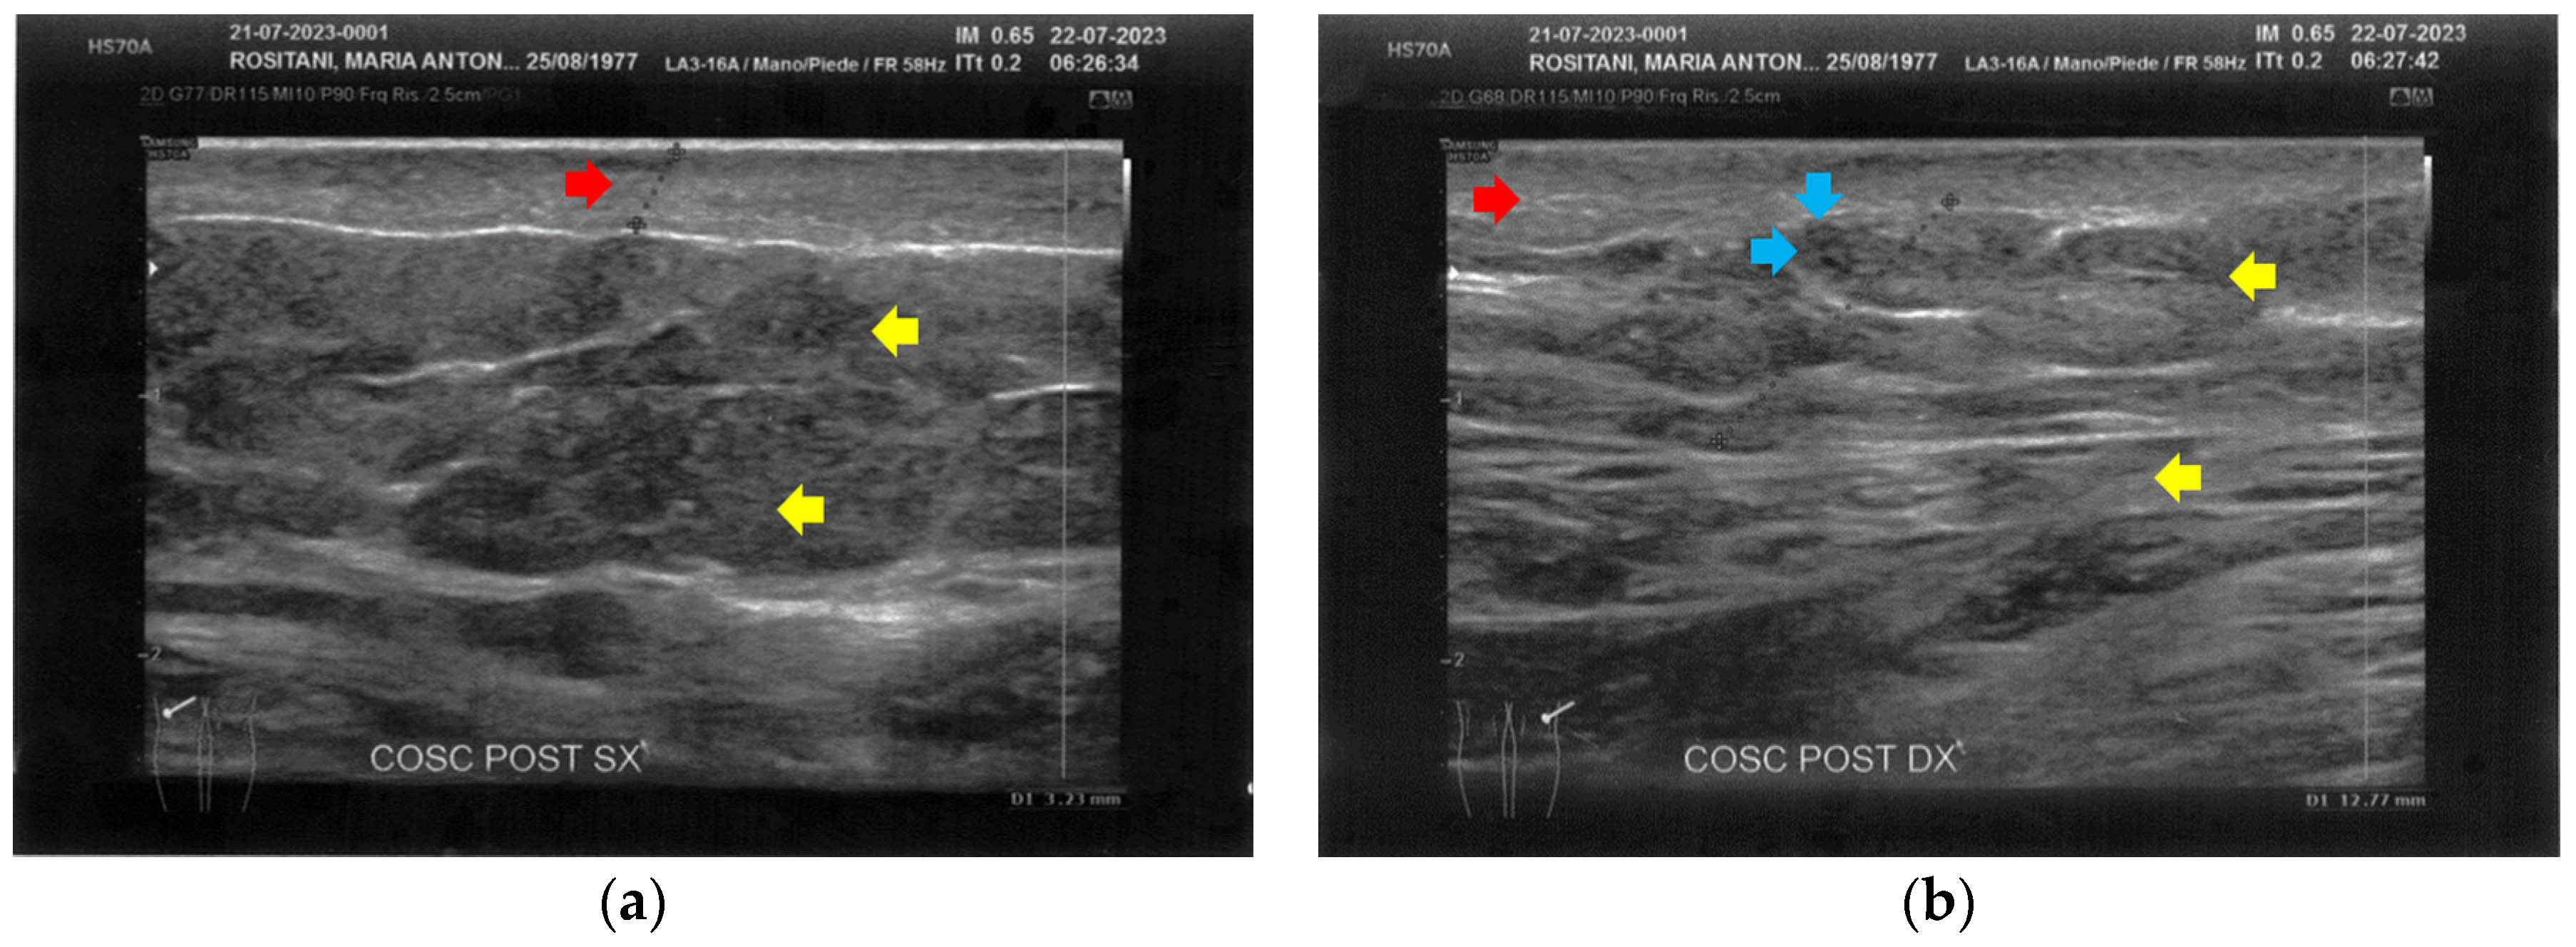

3.1. Basal Imaging Evaluations

3.2. Imaging Evaluations After the Treatment